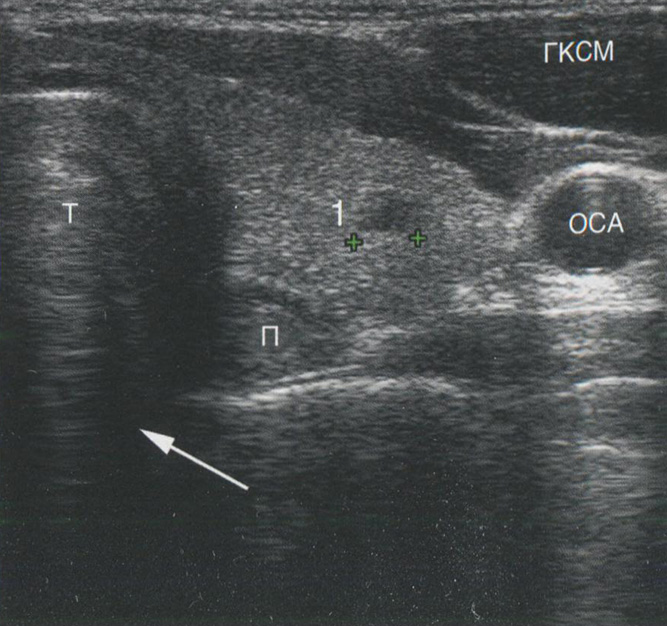

Когда звуковые волны попадают на область с сильно выраженной разницей акустического импеданса, например, на границу ткань-воздух или на кальцинат, подавляющее большинство звуковых волн отражается, обеспечивая очень яркий сигнал, исходящий от поверхности объекта, и отсутствие изображения за его пределами. Рис. 2.9 демонстрирует акустическую тень за кальцинированным узлом. На рис. 2.10 изображен грубый кальцинат в паренхиме щитовидной железы (ЩЖ) с акустической тенью позади кальцината. Рис. 2.11 показывает типичную картину

Рис. 2.11. Акустическая тень. Область кзади от трахеи не визуализируется во фронтальной проекции из-за очень высокого отражения на границе ткань-воздух. Т — трахея; П — пищевод; ГКСМ — грудино-ключично-сосцевидная мышца; ОСА — общая сонная артерия